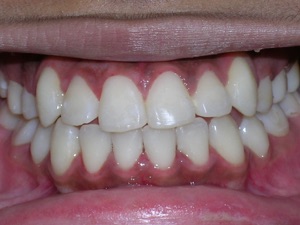

Here’s a young lady who presented with severe crowding. Often we think of crooked teeth as being limited to front teeth. Here one can see that back teeth can also get crowded. Braces were placed and select teeth were removed. Watch.